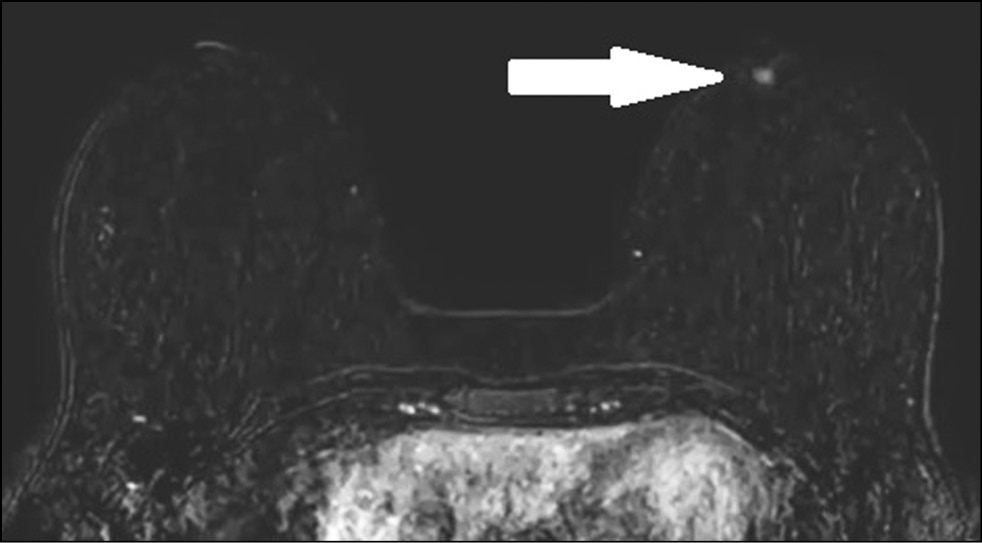

In a 43-year-old patient who had no complaints, the breast was examined by MRI to assess the integrity of implants. The asymmetric enhancement of the left nipple was accidentally found (Figs. 9 and 10). Three-year dynamic observation did not reveal any unfavorable changes.

Figure 9. Magnetic resonance imaging (early postcontrast series): asymmetric contrast accumulation in the left nipple; normal finding (arrow).

Figure 10. Magnetic resonance imaging (MIP): asymmetric contrast accumulation in the left nipple; normal finding (arrow).

Cases 3 and 4 prove that asymmetric contrast accumulation in MRI is not necessarily a sign of pathology. Normally, in MRI, both nipples accumulate the contrast agent at the same rate and intensity. However, nipple asymmetry may be the normal variation. Possible reasons include special NAC anatomy, breast size, breast compression and friction with clothing, blood flow variations, and local inflammation. [12] Aome physiological features and differences are involved in contrast accumulation in NAC structures. Both breasts usually show symmetrical thin rings of enhancement. In some cases, enhancement is asymmetrical in the early phase and becomes symmetrical in later phases. In a study of 530 normal nipples in 265 asymptomatic women, Gao et al. used T1-weighted NAC images to describe three areas of enhancement. [12]

Nipple inversion is a benign condition associated with the insufficient ability of the mesenchymal tissue to fix the nipple in the right position. [12] It occurs in 4% of women and men. Nipples are convex in 75% of women, flat in 23%, and inverted in 2%. MIP images are well suited for assessing the morphology and symmetry of the NAC. On postcontrast images, the nipple should be hypo- or isointense compared with the enhanced parenchymal tissue in the background. [12]